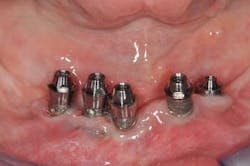

Fig. 11: For a better prosthetic outcome, the implants in site 26 and 27 have been extracted and replaced with two Biomet 3i® implants.

Fig. 12: A new implant impression is taken

Fig. 13a, b: The new master cast shows the modified implant situation